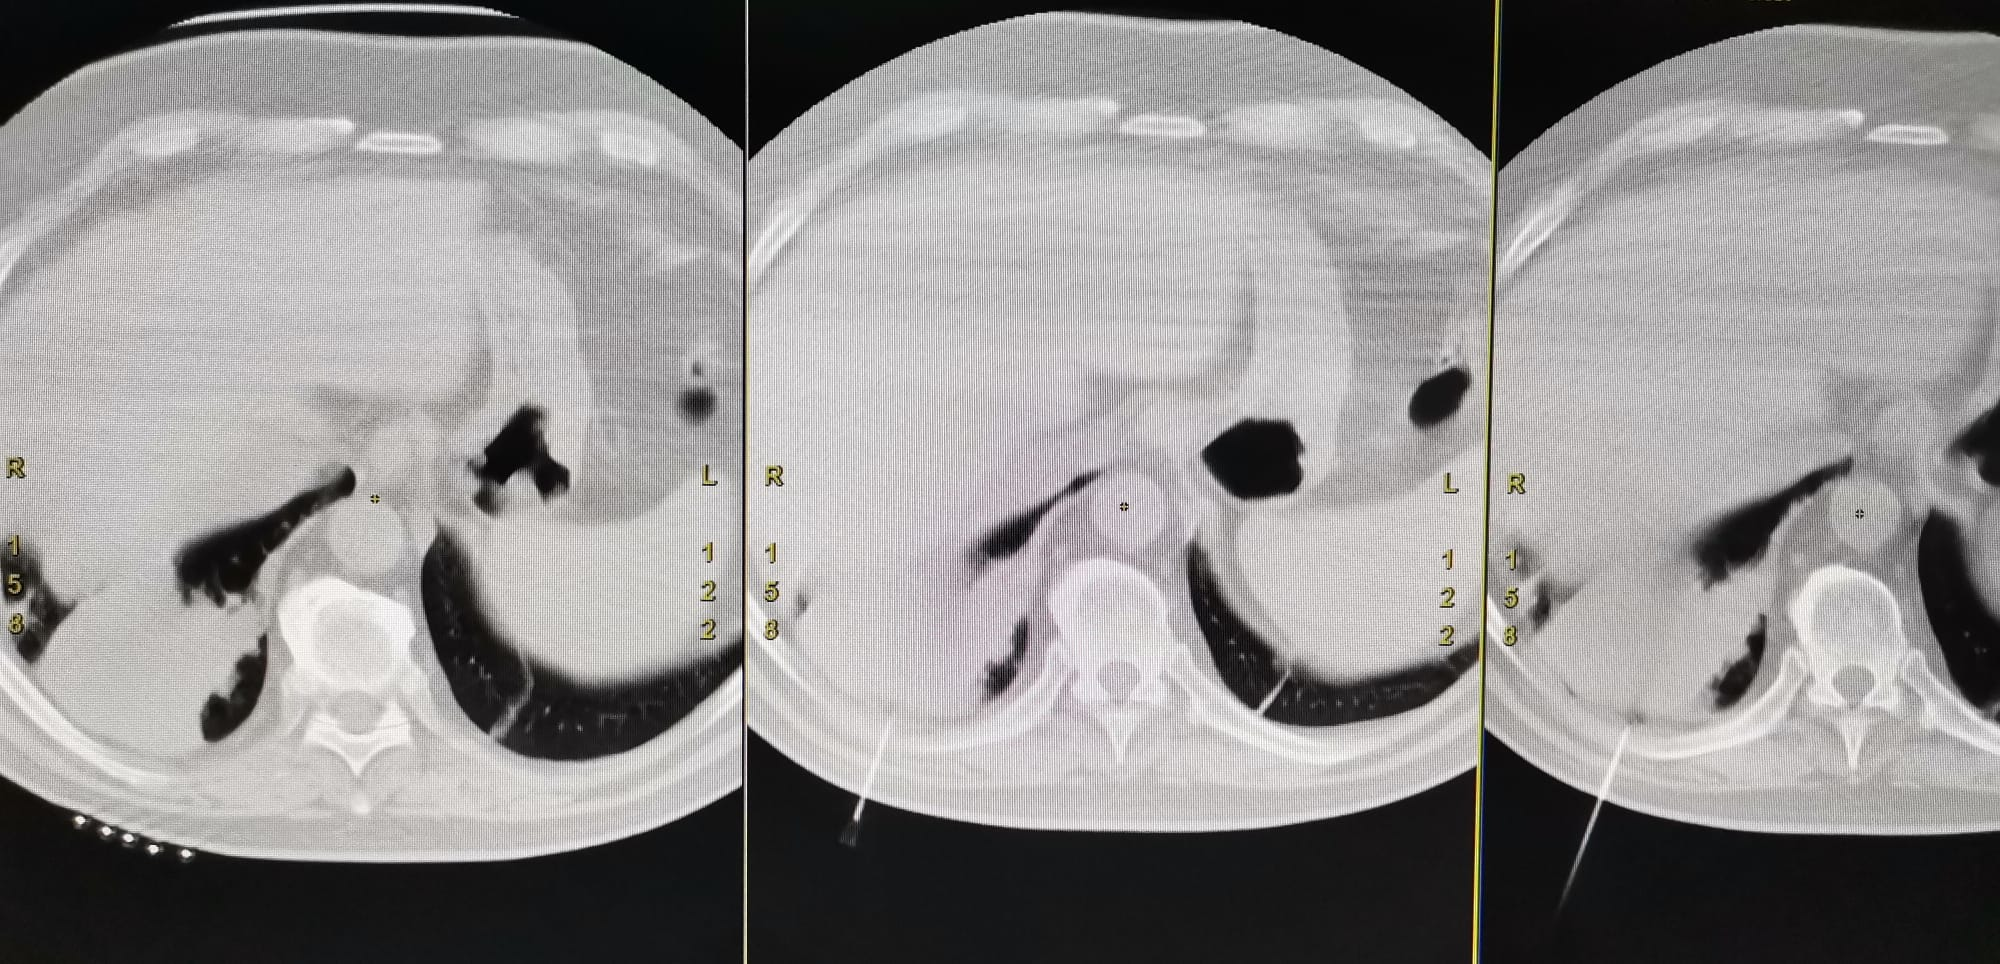

Prima biopsie pulmonară CT ghidată a fost realizată în cadrul Laboratorului de Radiologie și Imagistică Medicală, ca urmare a colaborării dintre medicii radiologi și chirurgii toracici ai Spitalului Clinic Județean de Urgență Sibiu.

Acest tip de biopsie este o intervenție minim invazivă care permite recoltarea, cu ajutorul unui ac de biopsie, a unui fragment de țesut dintr-o formațiune suspectă imagistic, sub ghidaj CT. Metoda este utilă pacienților cu formațiuni pulmonare neoplazice din Spitalul Clinic Județean de Urgență, pacienților din celelalte spitale din județul Sibiu, dar și din județele limitrofe.